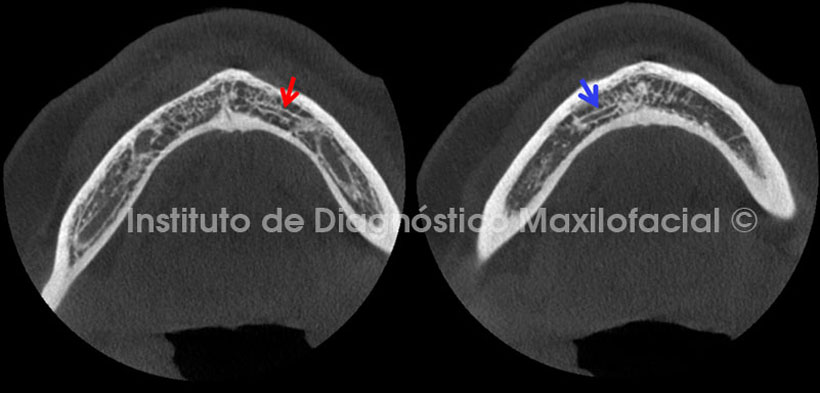

En cortes axiales (Fig.5) se aprecian ambos conductos incisivos mandibulares tanto del lado izquierdo (flecha roja) como del lado derecho (flecha azul). Dichos conductos se visualizan parcialmente en estos cortes ya que, como se observa en las imágenes anterios, esta estructura tubular presenta un trayecto irregular.